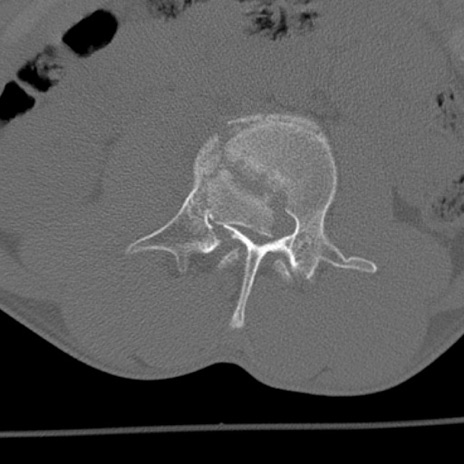

症例3 腰椎CT(横断像)

腰椎CT